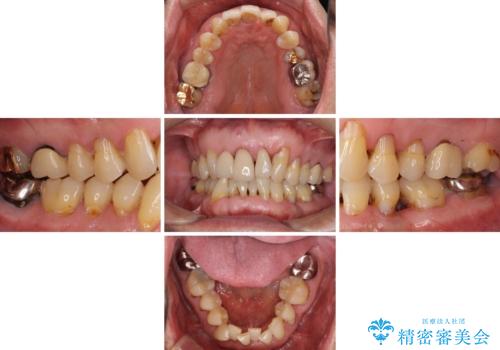

- 上の前歯が痛むとのことで来院された患者様です。

検査を行ったところ、前歯1本は周辺の骨が失われており、抜歯が必要でした。

上顎の奥歯は全体的に歯周ポケットが散見され出血が認められたため、歯周外科処置を行うこととしました。

上の歯は見た目を良くしたいというご希望があったため、歯周外科処置を行った歯についてはセラミッククラウンで補綴することとしました。

また、前歯の部分矯正も希望されたため、歯周外科処置と平行して矯正治療を行うこととしました。